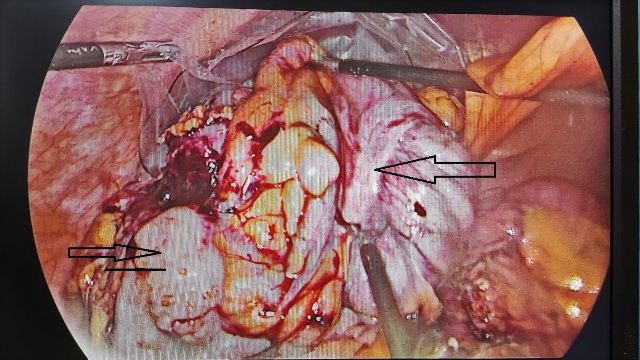

Bangalore: In an extremely rare case, doctors at Aster RV Hospital successfully conducted a multi-visceral resection surgery using a minimally invasive approach on a 45-year-old male suffering from colon cancer. Typically, such surgeries are conducted through an open incision however, the doctors decided to use a laparoscopic technique in Mr Shekhar’s (name changed) case, making this potentially the first of its kind in the country. According to medical literature, this type of surgery has previously been successfully performed only once in the world.

“Conventional methods like chemotherapy were not working on the patient and there was no reduction in disease or tumour size. PET scans revealed that the spread of the cancer was only local and the next step to treatment would be to excise the cancerous areas. Multi-visceral resection in such cases is a surgical treatment option that can cure the disease however this is a very technically challenging surgery. To the best of our knowledge, this is the most extensive multi-visceral laparoscopic resection and probably the first in India to be ever reported,” said Dr. Girish SP, Lead Consultant – General and GI Surgery, Aster RV Hospital. The surgery was conducted over a period of 360 minutes with an intra-operative blood loss of just about 250 ml